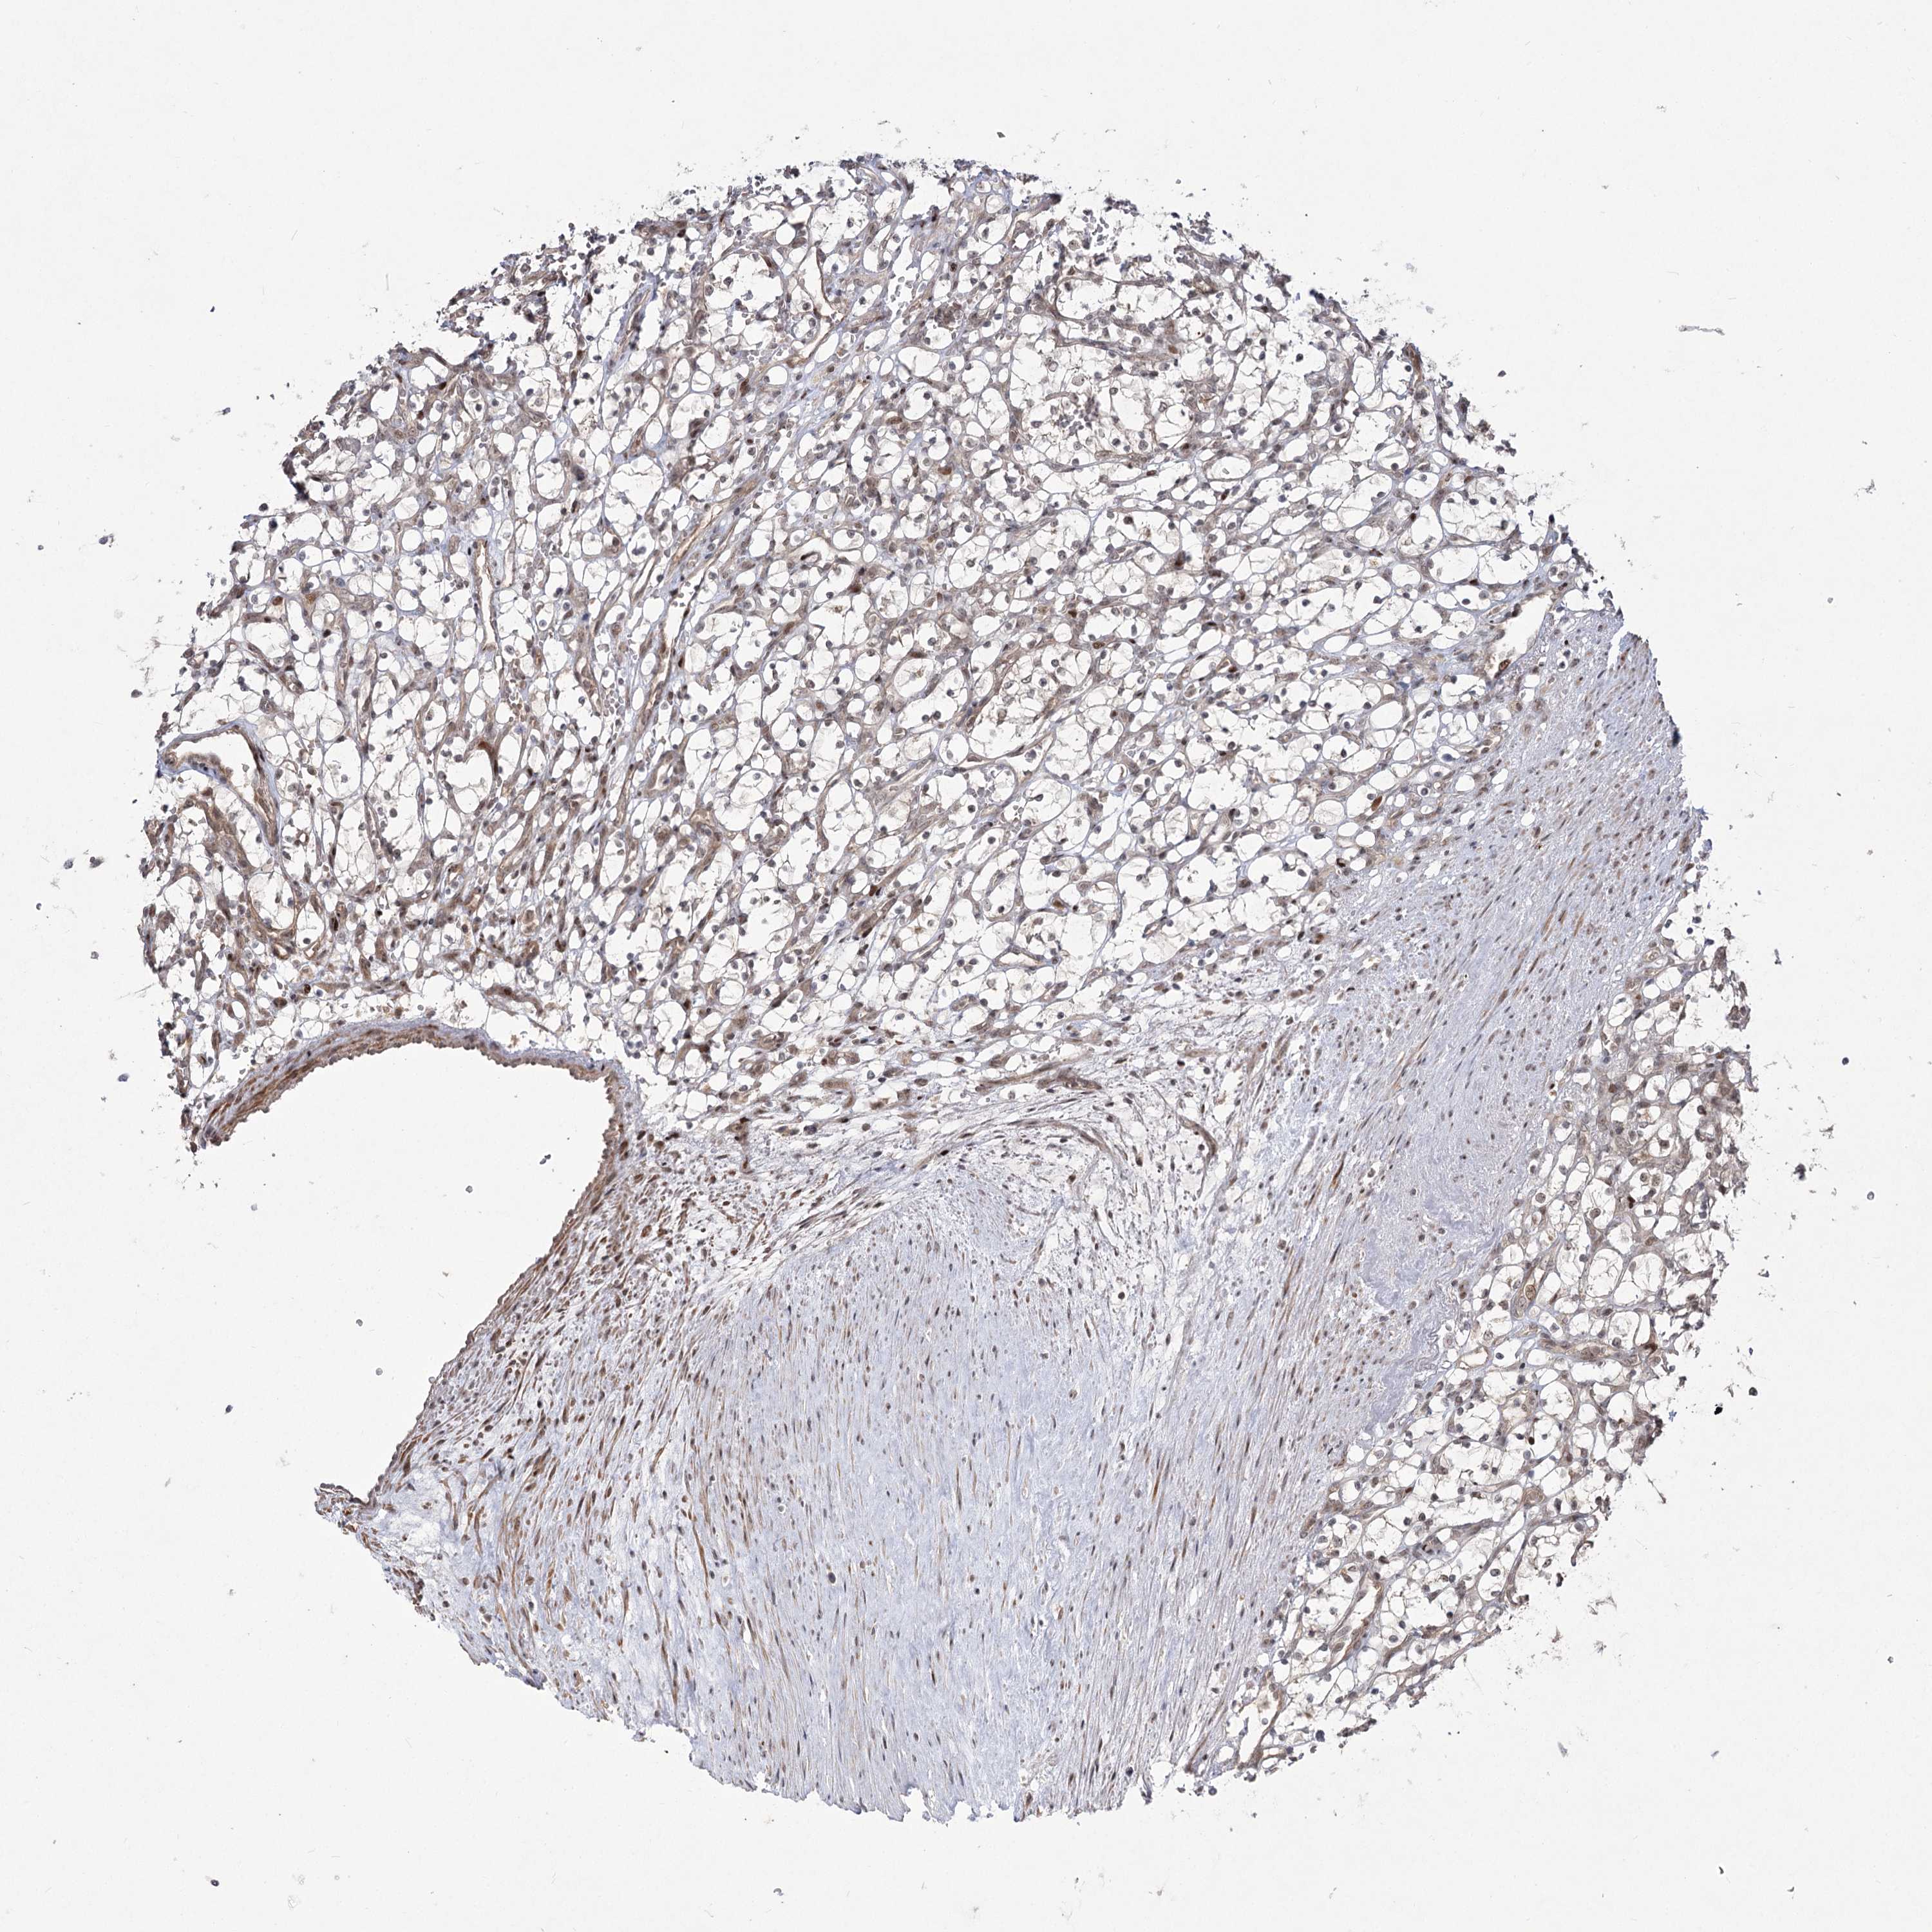

KIDNEY RENAL CLEAR CELL CARCINOMA (VALIDATION) - Interactive survival scatter ploti

The Survival Scatter plot shows the clinical status (i.e. dead or alive) for all individuals in the patient cohort, based on the same data that underlies the corresponding Kaplan-Meier plots. Patients that are alive at last time for follow-up are shown in blue and patients who have died during the study are shown in red.

The x-axis shows the expression levels (FPKM) of the investigated gene in the tumor tissue at the time of diagnosis. The y-axis shows the follow-up time after diagnosis (years). Both axes are complimented with kernel density curves demonstrating the data density over the axes. The top density plot shows the expression levels (FPKM) distribution among dead (red) and alive patients (blue). The right density plot shows the data density of the survived years of dead patients with high and low expression levels respectively, stratified using the cutoff indicated by the vertical dashed line through the Survival Scatter plot. This cutoff is automatically defined based on the FPKM cutoff that minimizes the p-score. The cutoff can be changed by dragging the vertical line or by entering a cutoff value in the square labeled "Current cut-off".

Under the Survival Scatter plot the p-score landscape (black curve; left axis) is shown together with dead median separation (red curve; right axis). Dead median separation is the difference in median mRNA expression between patients who have died with high and low expression, respectively. It is calculated as follows: median FPKM expression of dead patients with high expression - median FPKM expression of dead patients with low expression. This is intended to aid the user in visually exploring custom cutoffs and the associated p-scores and dead median separation.

Individual patient data is displayed and can be filtered by clicking on one or more of the category buttons on the top of the page. Categories describing expression level and patient information include: high, low, alive, dead, female, male and tumor stages. The scale of the x-axis can be toggled between linear and log-scale by clicking on the "x log" button. Mouse-over function shows TCGA ID, patient information and mRNA expression (FPKM) for each patient.

& Survival analysisi

Kaplan-Meier plots summarize results from analysis of correlation between mRNA expression level and patient survival. Patients were divided based on level of expression into one of the two groups "low" (under cut off) or "high" (over cut off). X-axis shows time for survival (years) and y-axis shows the probability of survival, where 1.0 corresponds to 100 percent.

HELQ is not prognostic in Kidney Renal Clear Cell Carcinoma (validation)

Best expression cut offi

Based on the FPKM value of each gene, patients were classified into two groups and association between prognosis (survival) and gene expression (FPKM) was examined. The best expression cut-off refers the FPKM value that yields maximal difference with regard to survival between the two groups at the lowest log-rank P-value. Best expression cut-off was selected based on survival analysis .

When clicking on this number, the vertical dashed line indicating cut-off, the interactive survival plot, and the Kaplan-Meier curve will be adjusted to show results based on the best expression cut-off.

: 6.65

P scorei

Log-rank P value for Kaplan-Meier plot showing results from analysis of correlation between mRNA expression level and patient survival.

N/A

5-year survival highi

5-year survival for patients with higher expression than the expression cutoff.

For melanoma and glioma, 3-year survival is shown.

5-year survival lowi

5-year survival for patients with lower expression than the expression cutoff.

TCGA RNA samplesi

RNA-seq data is reported as average FPKM (number Fragments Per Kilobase of exon per Million reads), generated by the The Cancer Genome Atlas (TCGA) .

Normal distribution across the dataset is visualized with box plots, shown as median and 25th and 75th percentiles. Points are displayed as outliers if they are above or below 1.5 times the interquartile range. FPKM values of the individual samples are presented next to the box plot.

Average pTPM 6.4

Number of samples 100